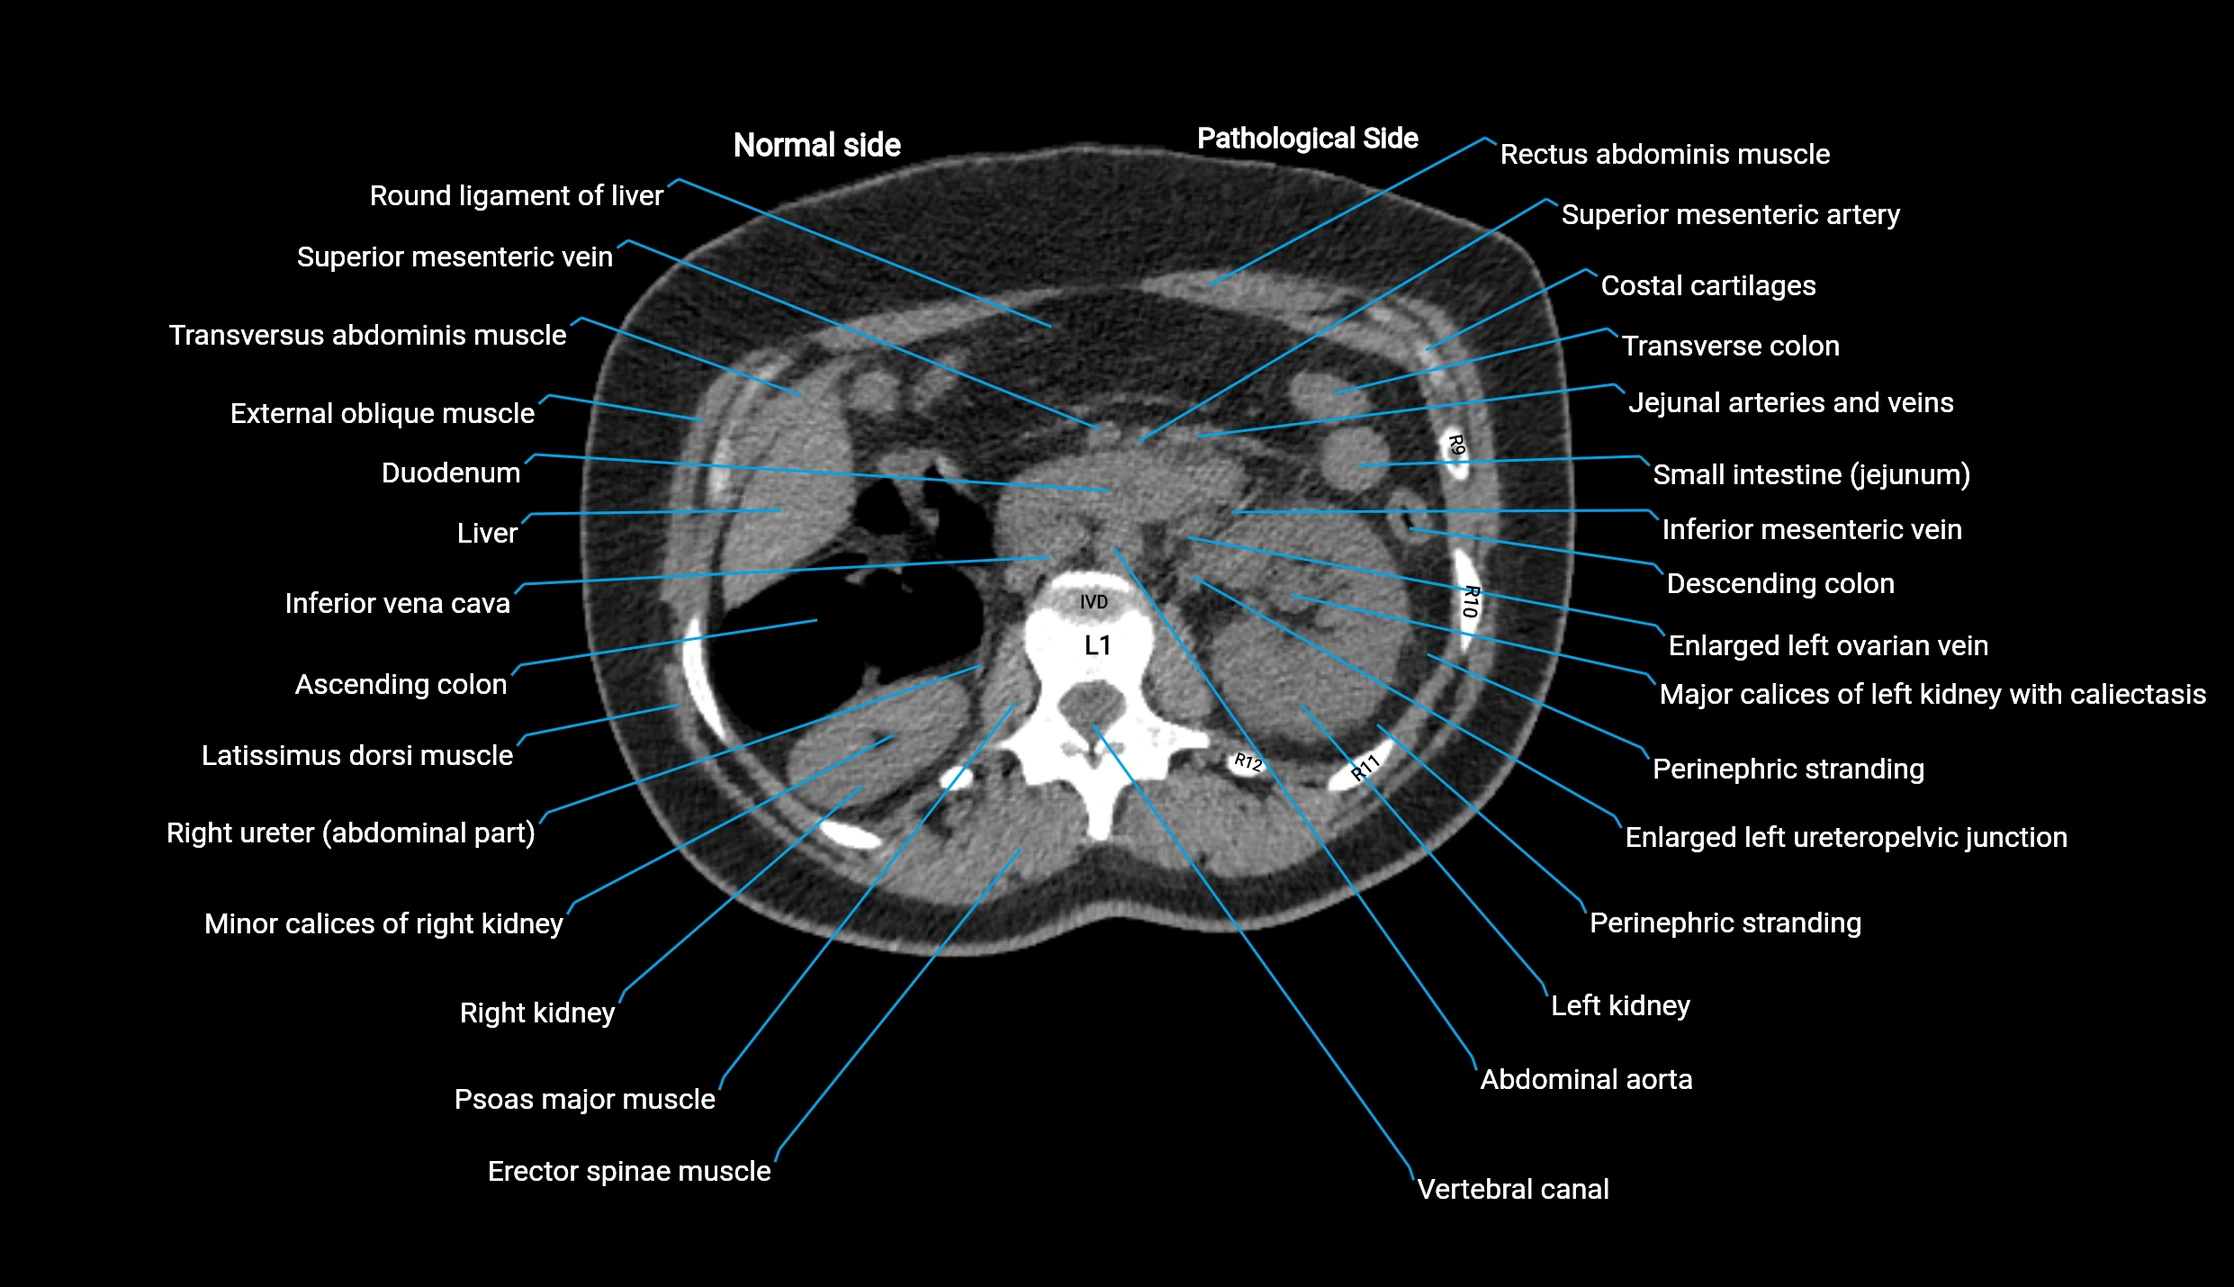

CT image

image